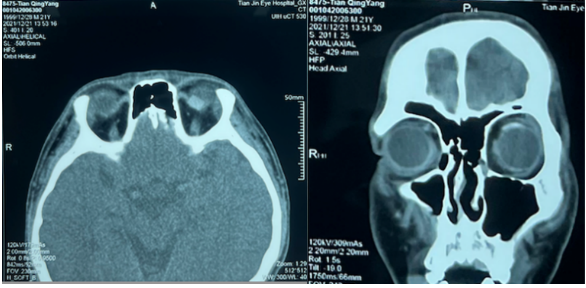

第一次手术记录及术后影像

4.勾全上斜肌,肌止端后1mm 6-0可吸收缝线双套环缝线,离断肌肉切断上斜肌,肌肉止端缝6mm硅胶带。

本次手术后